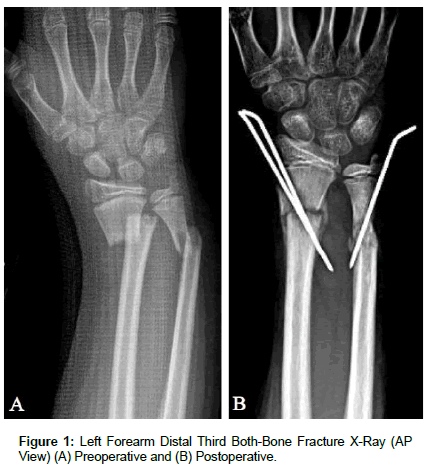

[04/13/2012] A 12-year-old Hispanic male was evaluated by the Orthopaedic Trauma service for a chief complaint of left forearm pain, after suffering a fall while playing soccer. The patient endorsed pain at the left wrist with range of motion, but denied constitutional symptoms and any other recent inciting trauma or injuries. On physical exam, the patient was noted to have a gross deformity of the left wrist and had tenderness to palpation overlying the distal radius and ulna. He was neurovascularly intact. Radiography (Figure 1) of the Left Upper Extremity (LUE) provided a definitive diagnosis of a skeletally immature individual with a closed distal radius and ulnar (both-bone) fracture with 100% displacement and 2 centimeters (cm) of shortening; subsequently the patient and his parents elected to pursue surgical intervention. Closed reduction and percutaneous pinning with placement of two 0.62 K-wires from the radial styloid distally to the medial aspect of the radial shaft proximally was performed to address the distal radius fracture and restore mechanical alignment. Closed reduction of the distal ulna fracture proved difficult so the procedure was converted to an open reduction through a direct approach to the ulnar fracture between the Extensor Carpi Ulnaris and Flexor Carpi Ulnaris. A 0.62 K-Wire was placed from distal to proximal through the ulnar shaft to restore mechanical alignment; dorsal comminution of the ulnar shaft was noted intraoperatively and consequently may have contributed to the difficulty with obtaining successful closed reduction.